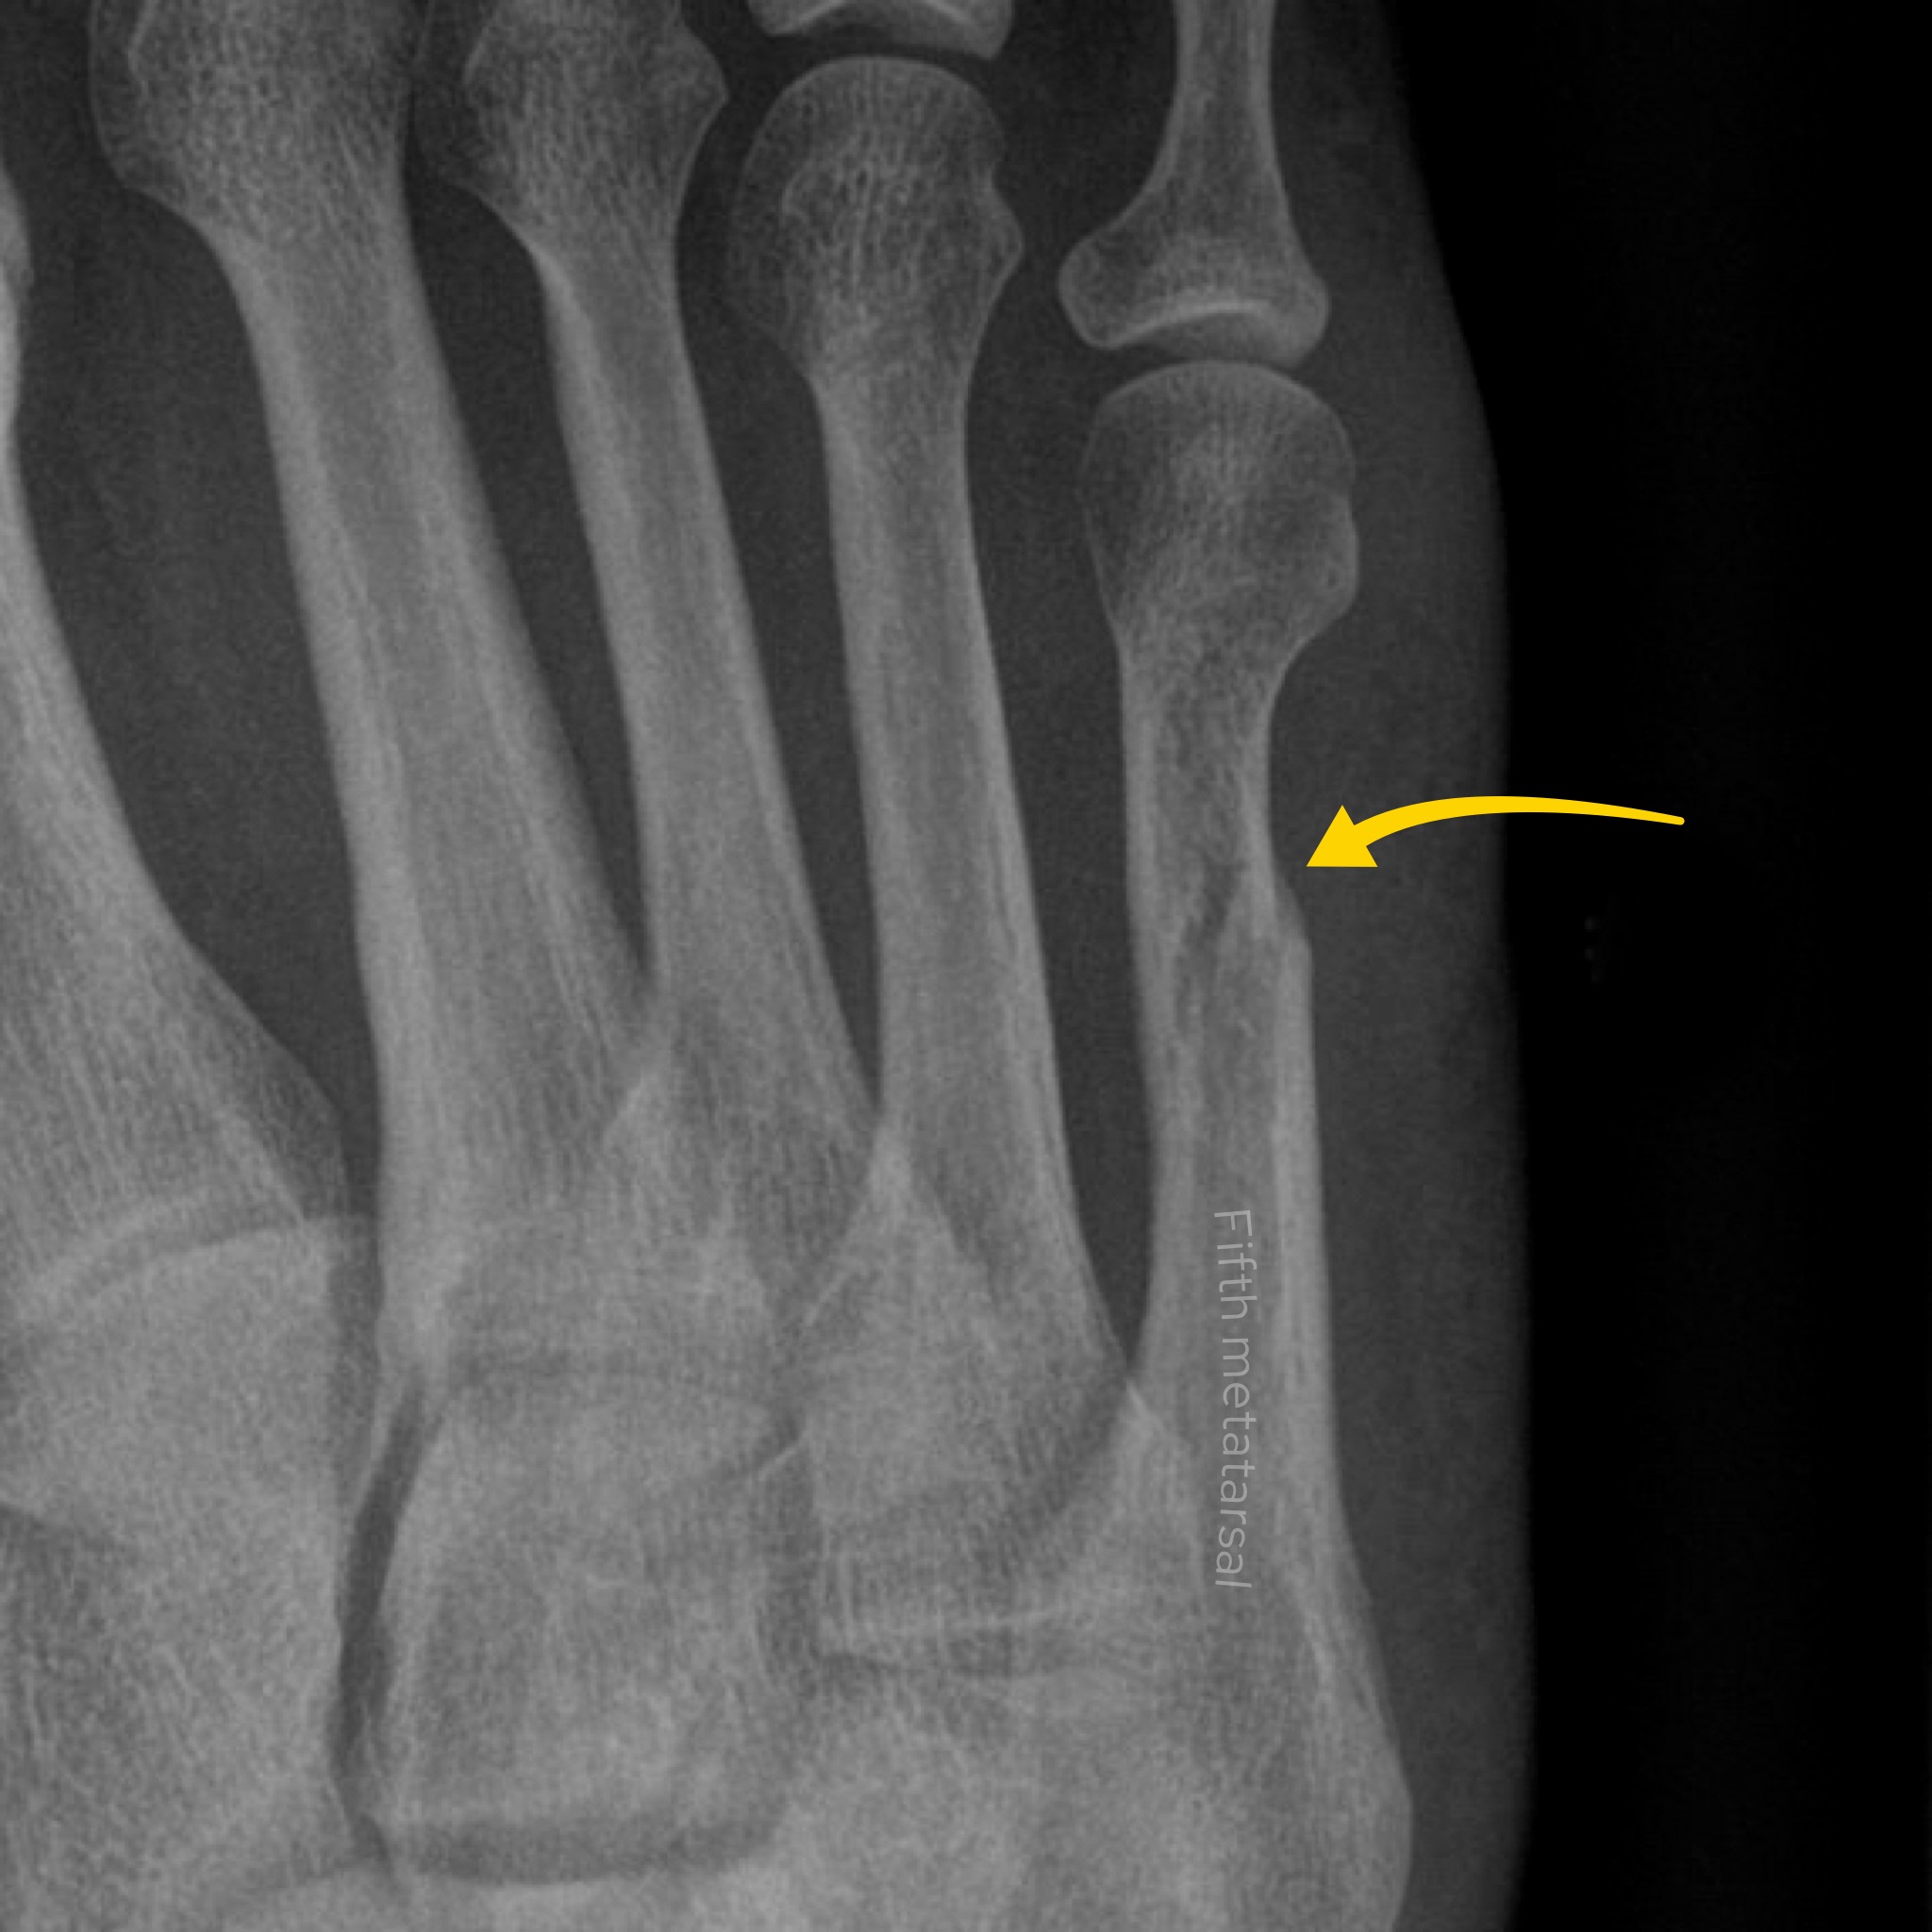

Case 7

A female in her 40s presents to the ED with foot pain after an episode of trauma. What does the foot X-Ray show?

Choose from one of the following: